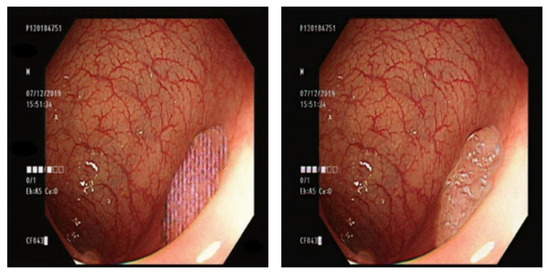

3.7. Comparison of GAN Output

4.1. Comparison of GAN-Generated Images